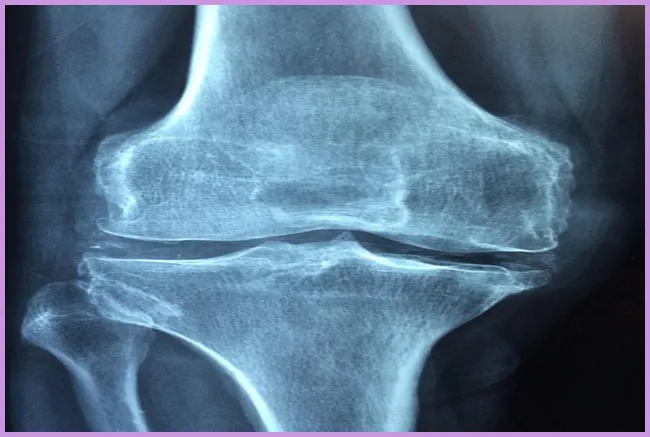

관절염 진단은 나이와 성별, 가족력 등의 다양한 요소를 고려하여 이루어집니다. 의사는 통증이 발생하는 관절을 검사하며, 필요한 경우 X선 촬영이나 혈액 검사를 통해 확실한 진단을 내릴 수 있습니다. 관절염 치료법으로는 비스테로이드 항염증제(NSAIDs)나 스테로이드 주사와 같은 약물치료가 있습니다.